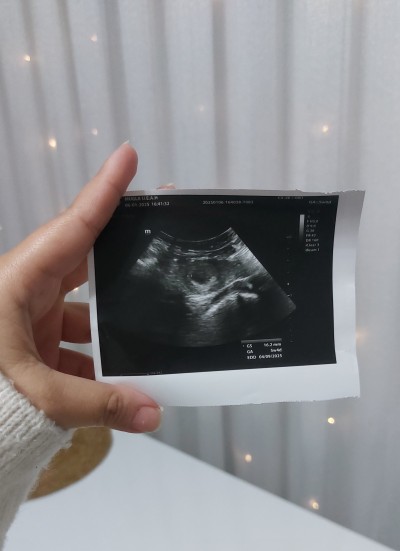

Merhaba  5 haftalık hamileyim buda ultrason görüntüsü eğitim araştırmadaki bi doktora gittim bilirsiniz ki özel hastane gibi detaylı bilgi vermiyorlar

Kese var haftaya gel kalp atışını dinleyelim deyip gönderdi

Anlayanlar var mı acaba burada yolk sac veya fetuse dair bir bulgu görebiliyor musunuz ben hiç anlamıyorum yardımcı olabilecek varmı

Gebelik haftası 5